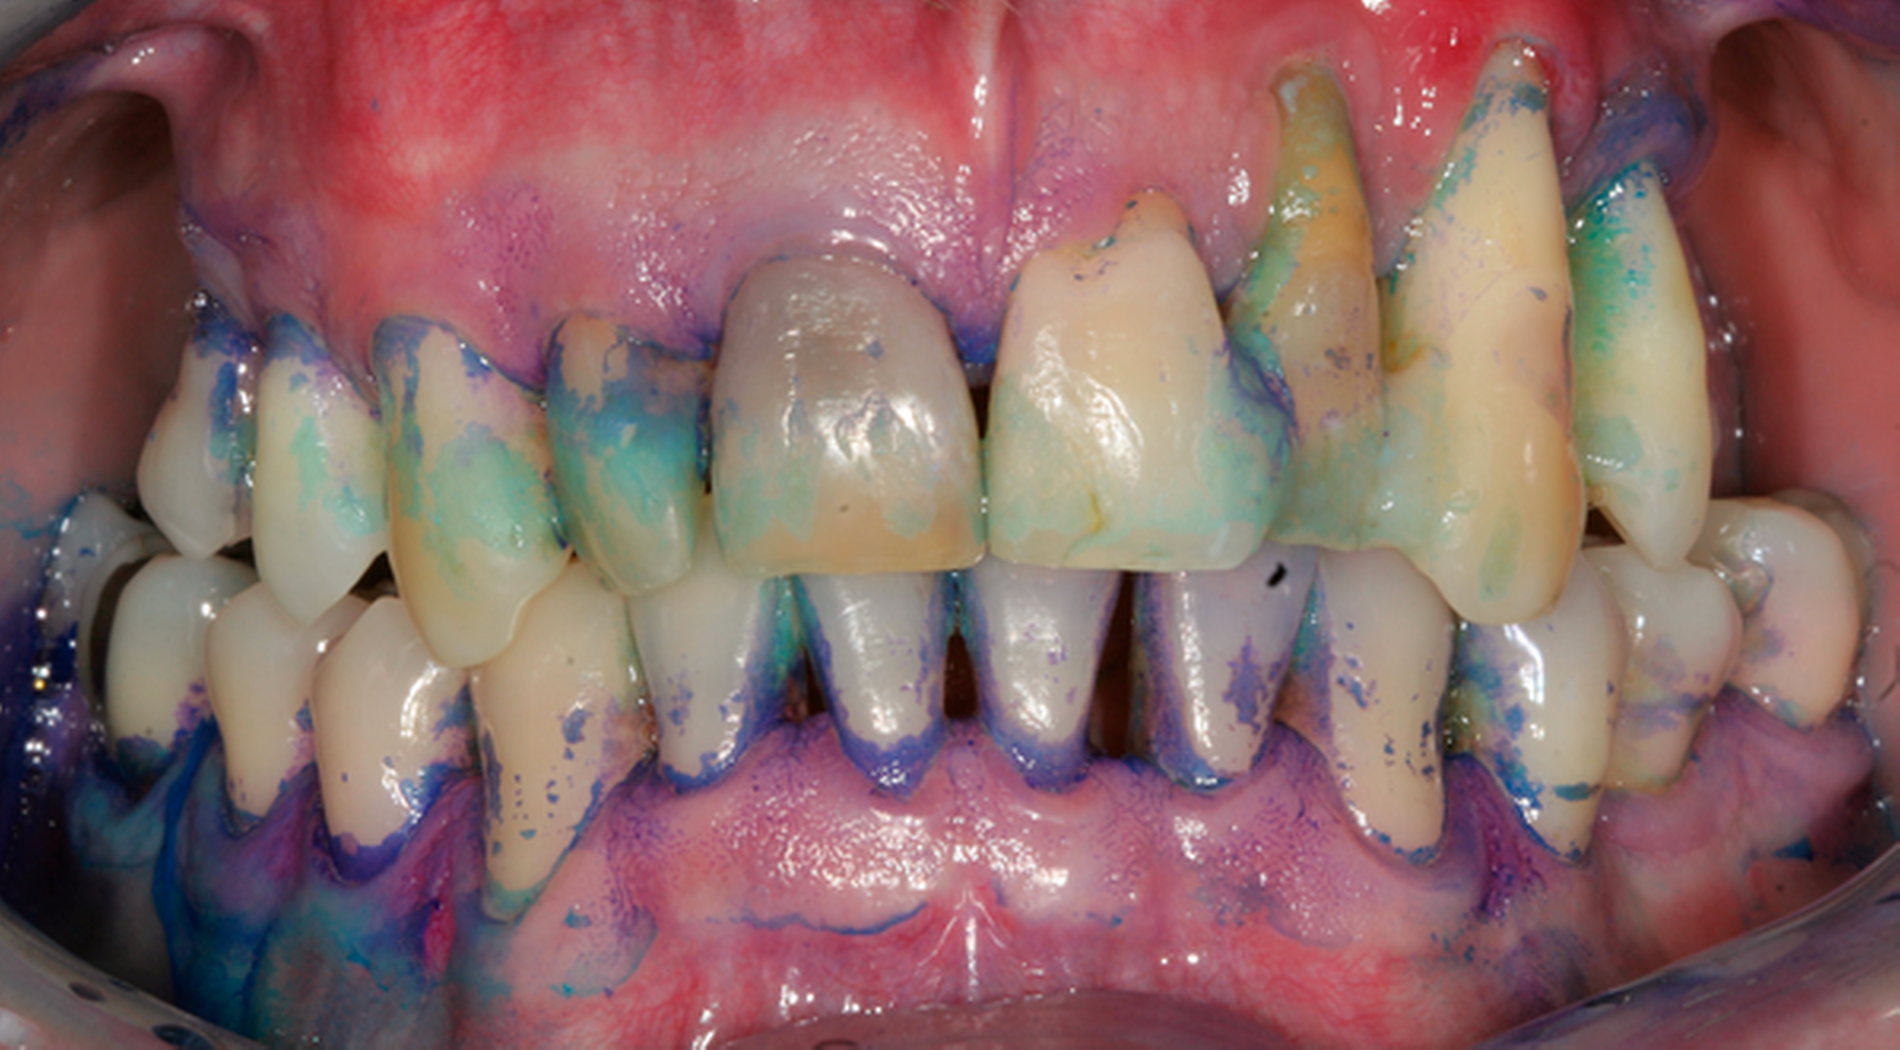

Abb. 2: Professionelle mechanische Plaquereduktion während einer UPT-Sitzung bei einem 50-jährigen Patienten mit reduziertem, aber gesundem Parodont im dritten Jahr nach zweiter Therapiestufe: